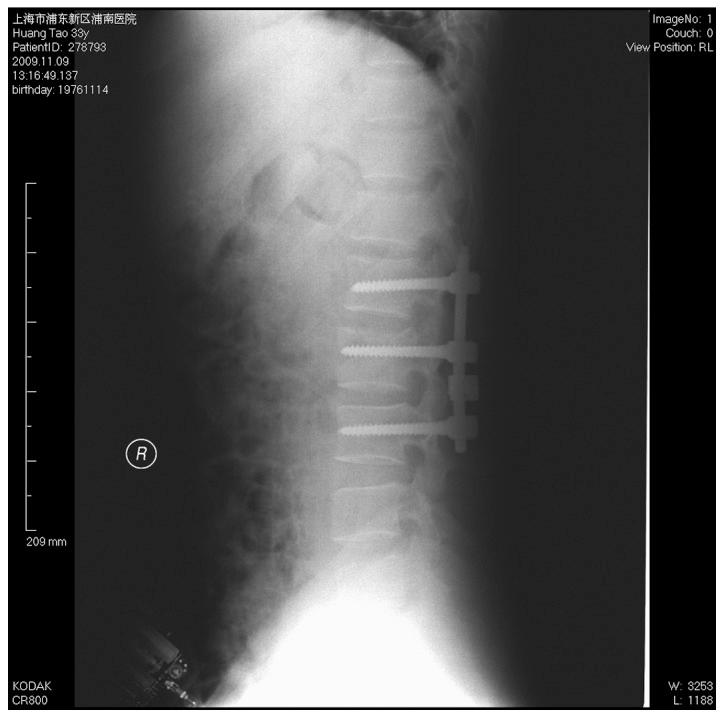

椎弓根螺钉内固定治疗胸腰椎骨折中骨折椎体的疗效分析

Efficacy analysis of pedicle screw internal fixation of fractured vertebrae in the treatment of thoracolumbar fractures.

The present study aimed to discuss the method and effect of posterior internal fixation of thoracolumbar fractures strengthened by the vertical stress pedicle screw fixation of fractured vertebrae. Patients with single thoracolumbar fractures were examined retrospectively. Fourteen patients (group A) had been treated with vertical stress pedicle screw fixation of a fractured vertebra and sixteen patients (group B) received traditional double-plate fixation, as a control. All patients were diagnosed with fresh fractures with a complete unilateral or bilateral pedicle and no explosion of the inferior half of the vertebral body or inferior endplate. In group A, patients received conventional posterior distraction and lumbar lordosis restoration, as well as pedicle screws in the fractured vertebra in a vertical direction to relieve stress to achieve a local stress balance. All patients were followed up postoperatively for 4-18 months (average, 12.6 months). The vertical stress pedicle screw fixation assisted in the reduction of vertebrae fracture, which reduced the postoperative Cobb's angle loss. There was a significant difference in the change of Cobb's angle between the two groups one year after surgery (P<0.01). Conditional application of pedicle screws in a single thoracolumbar fracture enhances the stability of the internal fixation system and is conducive to the correction of kyphosis and maintenance of the corrective effects.

摘要

本研究旨在探讨通过骨折椎体垂直应力椎弓根螺钉固定加强胸腰椎骨折后路内固定的方法及效果。对单节段胸腰椎骨折患者进行回顾性研究。14例患者(A组)采用骨折椎体垂直应力椎弓根螺钉固定治疗,16例患者(B组)接受传统双钢板固定作为对照。所有患者均诊断为新鲜骨折,单侧或双侧椎弓根完整,椎体下半部及终板无爆裂。A组患者接受传统后路撑开及腰椎前凸恢复,并在骨折椎体垂直方向置入椎弓根螺钉以缓解应力,实现局部应力平衡。所有患者术后随访4 - 18个月(平均12.6个月)。垂直应力椎弓根螺钉固定有助于椎体骨折复位,减少术后Cobb角丢失。术后1年两组Cobb角变化差异有统计学意义(P<0.01)。单节段胸腰椎骨折有条件地应用椎弓根螺钉可增强内固定系统稳定性,有利于后凸畸形的矫正及矫正效果的维持。